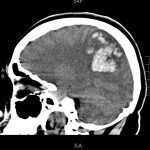

The patient’s head CT showed a significant area of hyperdensity consistent with an intracranial hemorrhage located within the left frontal parietal lobe (red arrow). Additionally, there is rightward midline shift up to 1.1cm (green arrow) and entrapment of the right lateral ventricle (blue arrow).